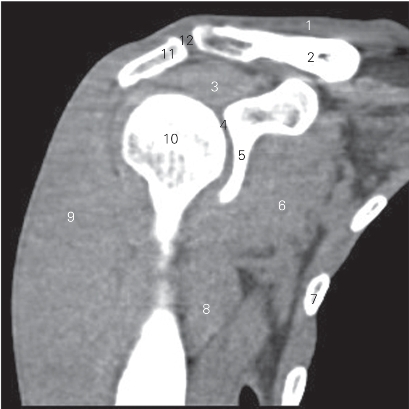

图4-1 经肩关节下份的横断层CT图像(软组织窗)

1 锁骨 clavicle 2 喙肱肌 coracobrachialis

3 关节盂 glenoid cavity 4 肩胛骨 scapula

5 肩胛下肌 subscapularis 6 三角肌 deltoid

7 冈下肌 infraspinatus 8 肩关节腔 cavity of shoulder joint

9 肱骨头 head of humerus

10 肱骨小结节 lesser tubercle of humerus

11 肱骨大结节 greater tubercle of humerus